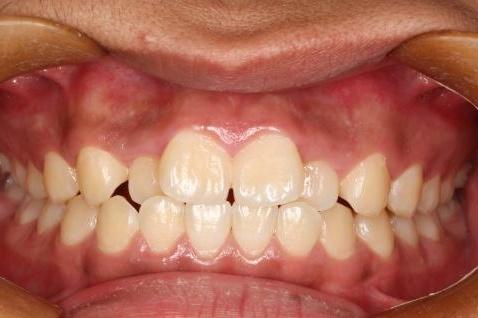

远移磨牙后排齐效果

对于面型尚可的轻中度拥挤患者可以通过微种植钉远移磨牙排齐牙列。